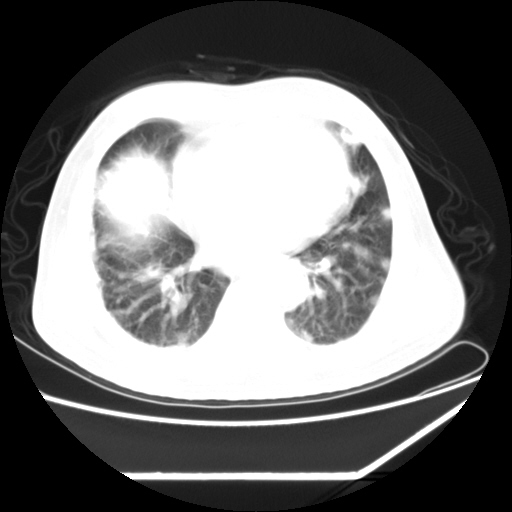

男,57,畏寒,发热

双肺多发结节样病灶,部分内见透光区,纵隔内见淋巴结肿大。结核临床如有畏寒,高热,白细胞增高首先考虑迁徙性肺脓肿(多是金黄色葡萄球菌感染)。

注意除外转移瘤。

1)考虑两肺感染性病变(金黄色葡萄球菌肺炎?);建议抗炎治疗后复查排除其他。2)双侧少量胸腔积液。

双肺典型的亚急性粟粒性肺结核

双侧胸膜结核